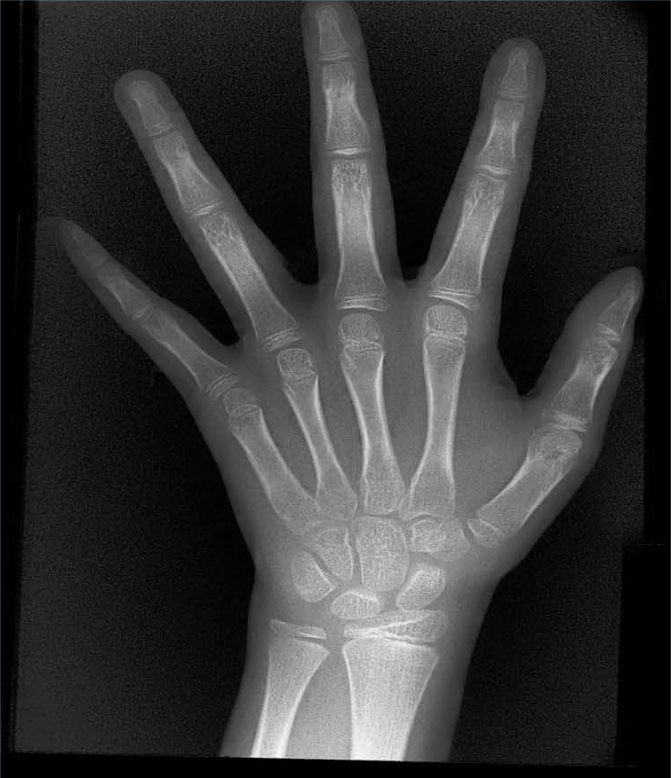

X射線骨齡儀通過拍攝兒童手腕部(指骨、掌骨、腕骨)的X射線影像,依據骨骼的形態(tài)、大小、鈣化程度等特征,結合評估標準(如《中國青少年兒童手腕骨成熟度及評價方法》,簡稱《中華-05》標準)進行骨齡判定。相較于傳統(tǒng)檢測方式,X射線骨齡儀具有輻射劑量低、影像清晰度高、檢測效率高的優(yōu)勢,能精準捕捉骨骼發(fā)育的細微變化,為骨齡評估的準確性提供保障。